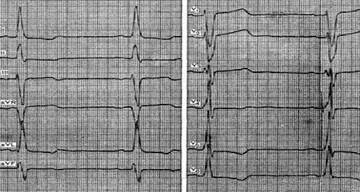

| 4-14 Ритм синусовый, гипертрофия, левого предсердия, правого желудочка,

| 7-16 Ритм синусовый, гипертрофия левого предсердия и левого желудочка

| 13-17Ритм синусовый, гипертрофия левого желудочка

| 17-14 Ритм синусовый, гипертрофия левого желудочка, систолическая перегрузка